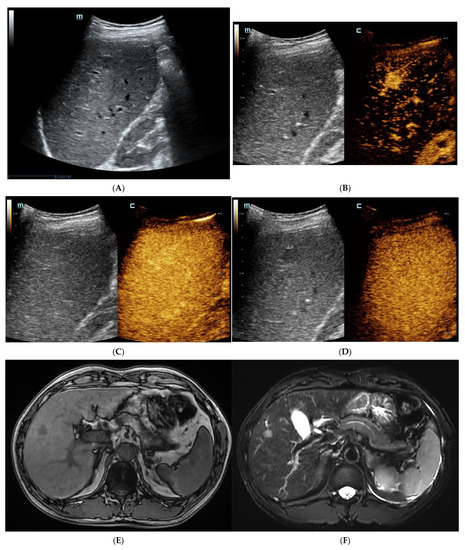

Figure 2.

The contrast-enhanced images of non-steatohepatitic hepatocellular carcinoma (non-SH-HCC). A hypo-echoic lesion in the right lobe of the liver was seen as seen via BMUS (A). In the early arterial phase of CEUS, the hepatic nodule was homogeneously hyperenhanced (B). During, it presented continuous iso-enhancement during the portal venous and late phase (C,D). On T1WI, the hepatic nodule was homogeneous hypointense (E). On T2WI, it was hypointense (F). As seen via con-trast-enhanced scan, the lesion showed hyperintensity in the arterial phase (G). It exhibited slight hyperintensity in the portal venous phase (H). During the late phase, the hepatic lesion started to show iso-intensity (I).